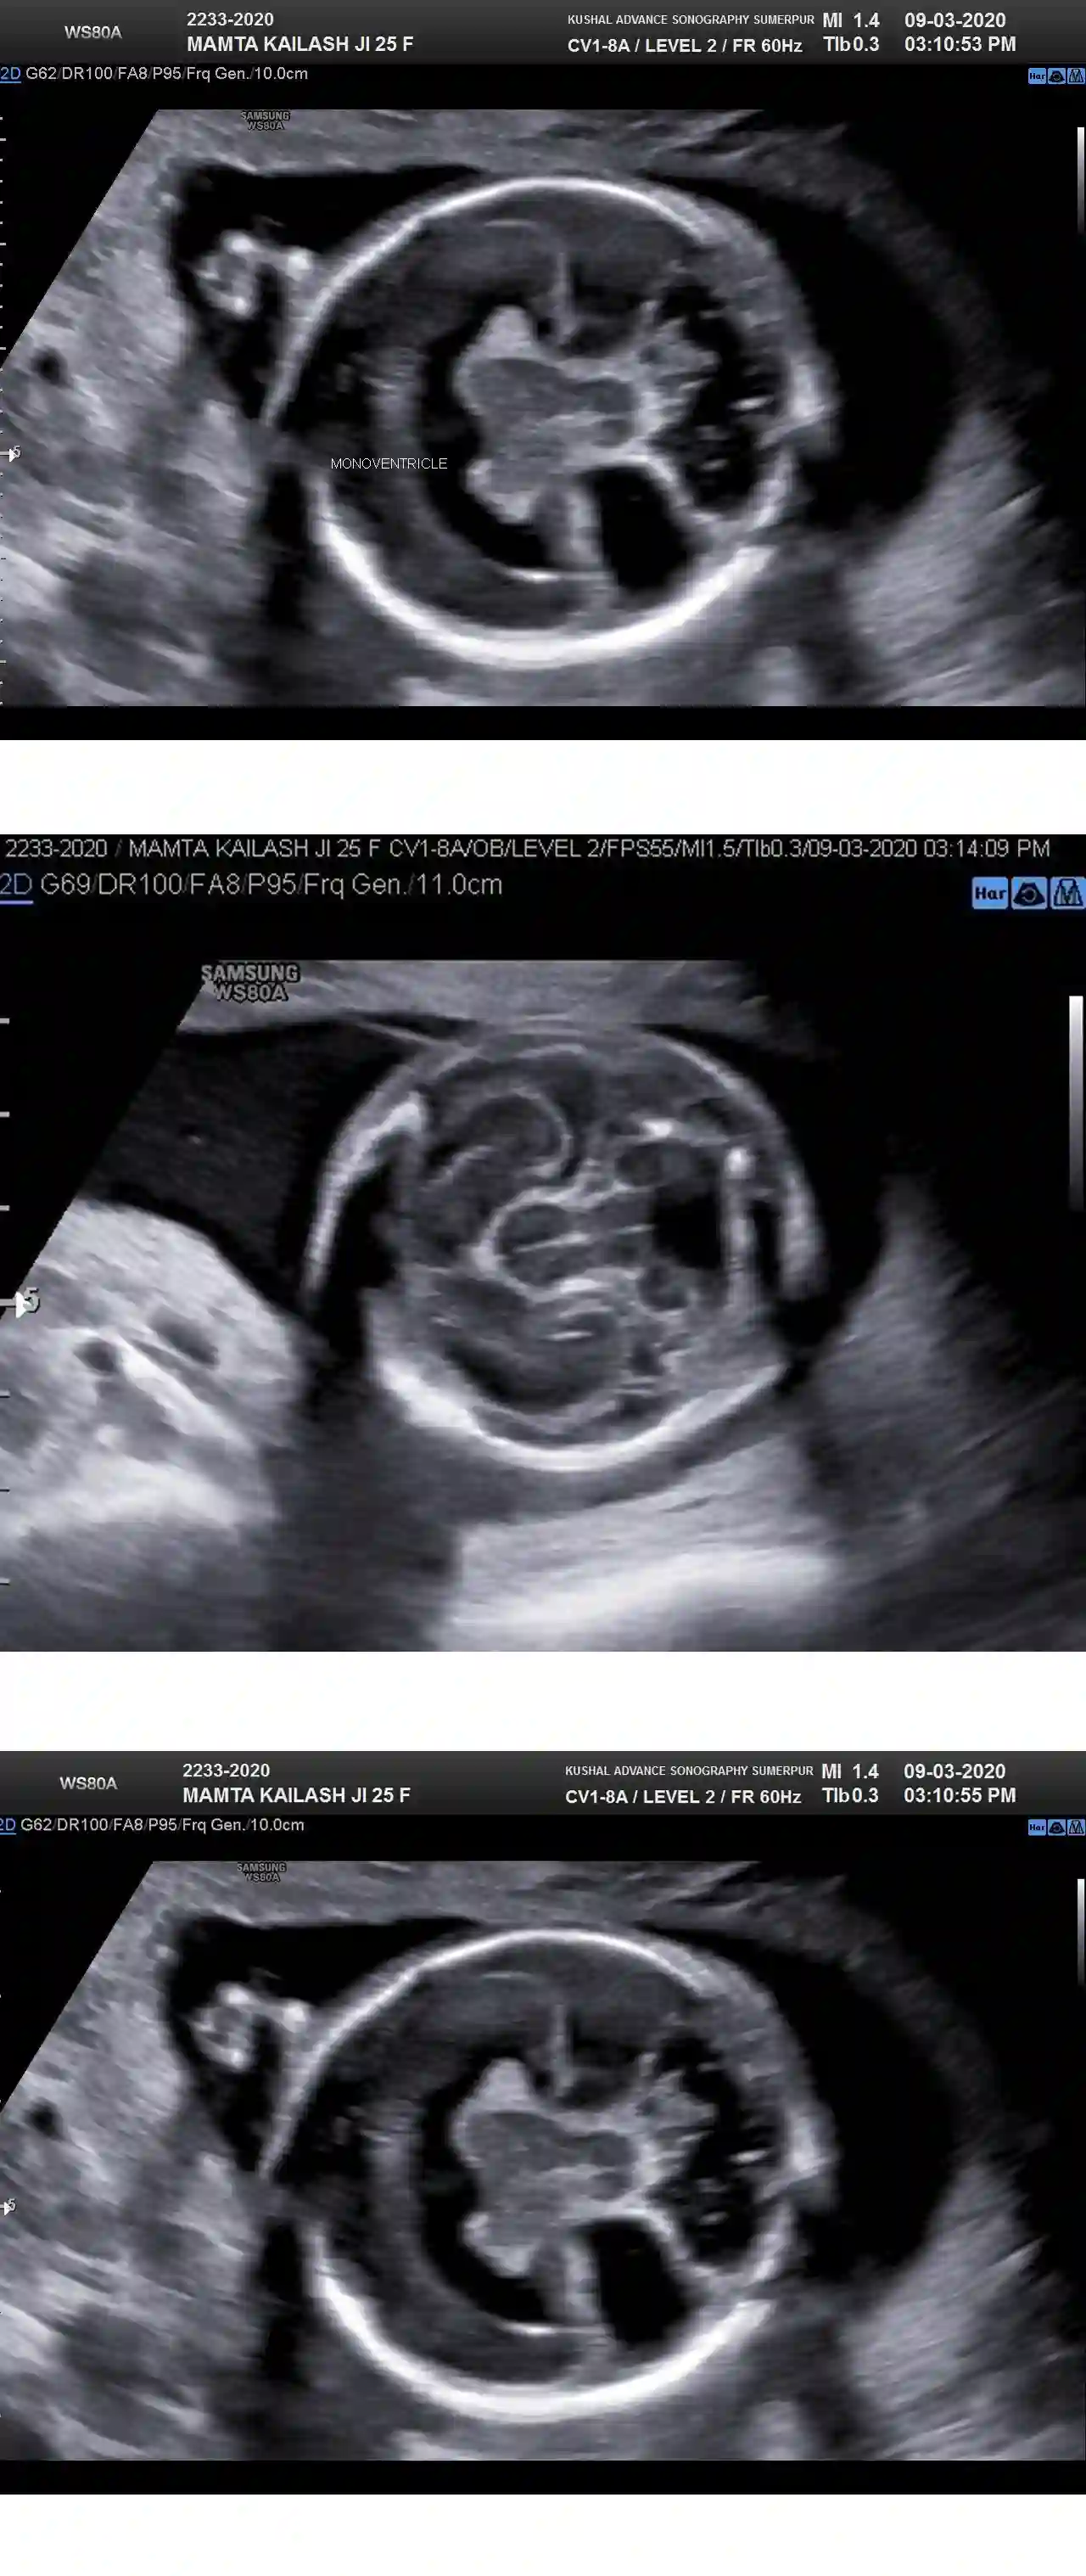

Alobar Holoprosencephaly.

The alobar holoprosencephaly is the most severe form and shows undifferentiated holosphere of the cerebral parenchyma with a central monoventricle and fused thalami. The falx, interhemispheric fissure, corpus callosum, optic tracts, olfactory bulbs, and the septum pellucidum are absent. Absence of septum pellucidum may be associated with septooptic dysplasia, holoprosencephaly, corpus callosal agenesis, schizencephaly, Chiari-II malformation, hydranencephaly, porencephaly, and cephaloceles.